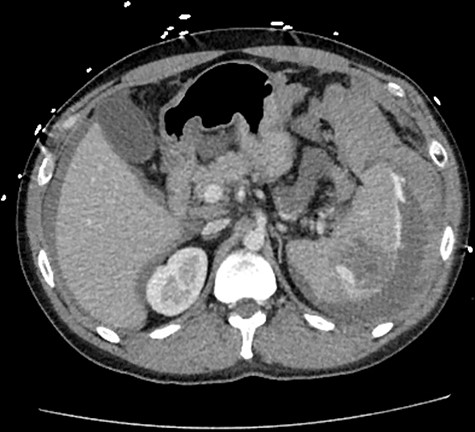

A 33-year-old male arrived to the emergency department complaining of sudden onset, severe, left upper quadrant abdominal pain. He was found to be hypotensive, pale and diaphoretic. His history was negative for recent trauma, travel or use of anticoagulation medications. Family history per patient was unremarkable, including that of coagulopathies. Treatment was initiated with crystalloid fluid bolus with appropriate improvement in blood pressure but persistent tachycardia. His physical exam was pertinent for mild abdominal distention and tenderness localized to the left upper quadrant without additional signs of peritonitis. Initial workup revealed a hemoglobin (Hgb) concentration of 6.5 mg/dL and a lactic acid level of 5.7 mg/dL. A bedside ultrasound conducted by the treating emergency room physician revealed perisplenic fluid concerning for spontaneous splenic hemorrhage. Transfusion of packed red blood cells (PRBC) was initiated with transient hemodynamic response allowing for computed tomography (CT) scan of the chest, abdomen and pelvis to be complete. As demonstrated (Fig. 1), this revealed moderate volume hemoperitoneum and intrasplenic pseudoaneurysm with active arterial extravasation consistent with a grade IV splenic injury.

CT abdomen with intravenous contrast, axial view, demonstrating intrasplenic pseudoaneurysm with active arterial extravasation.